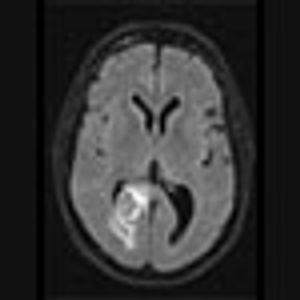

Image IQ: 73-year-old with History of Lung Mass Suffers Headaches

A 73-year-old male with history of a lung mass on recent chest radiograph presents with headaches.